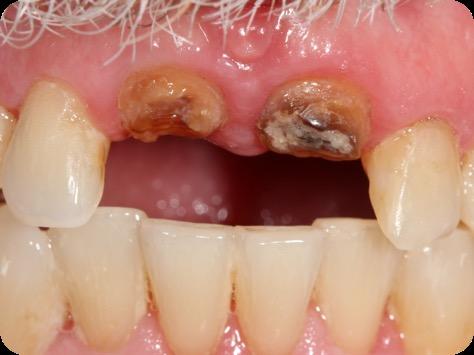

This case was performed by Dr Homa Zadeh, DDS, PhD, a respected leader in periodontology and implant dentistry. Dr Zadeh’s approach emphasizes biologically driven protocols and evidence-based techniques, making this case a strong example of clinical excellence using the Tapered Pro Conical system. It involves the replacement of two front anterior teeth after they fractured off and the full restoration process.

Fig 1. Patient anterior situation. Two anterior crowns fractured off.

Fig 2. Intraoral radiograph indicating tooth structural loss extent.

Fig 3. Provisional restorations on central incisors and gingival images. The gingival contours were optimal, and the gingival phenotype was thick.

Fig 4. Alveolar bone imaging. The alveolar bone was intact, and the alveolar crest was approximately 4mm apical to the restorative margin.